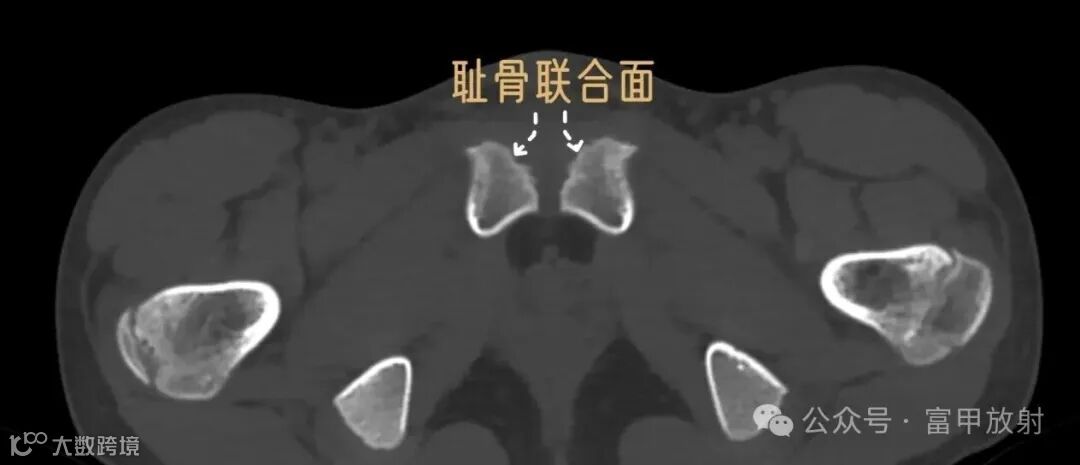

耻骨下支与坐骨分界在哪里?

坐骨结节是坐骨支的突起,是腘绳肌等附着的地方,耻骨结节是耻骨上支内侧缘的突起,腹股沟韧带附着点,在X线上坐骨结节也许估计到,耻骨结节基本上找不到,在这基础上作测量定位置,可靠性会不理想。以下这个简单的方法也许可以帮助到你。